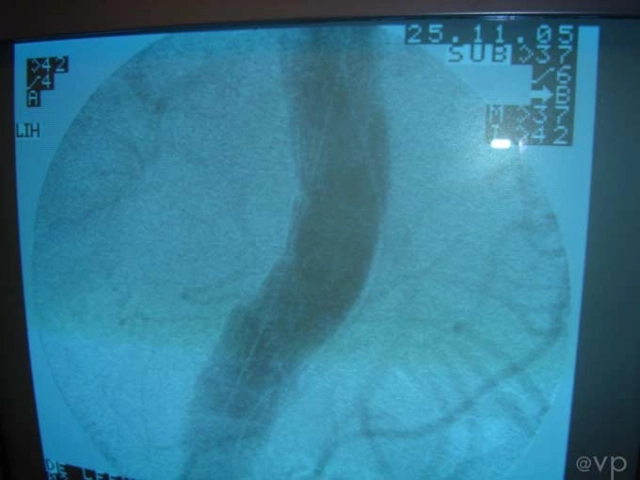

Intestinal

| Hybrid